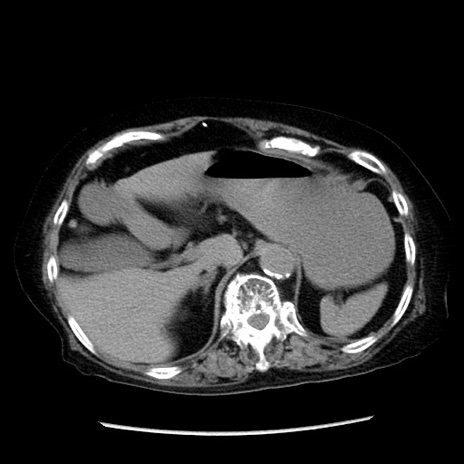

冠状断像

症例14(横断像)

【症例】 90歳代女性

【主訴】 腹痛・嘔吐

【現病歴】今朝から左側腹部痛を認めた。 経過観察していたが、嘔吐を認めたため来院。

【既往歴】 子宮癌術後

【身体所見】 意識清明、BP 127/54mmHg、P 98bpm Sp02 95%(RA)、BT 35.8°C、腹部平坦・軟腸ぜん動音聴取良好、右下腹部圧痛(+) 反跳痛なし

【データ】WBC 9800、CRP 0.46